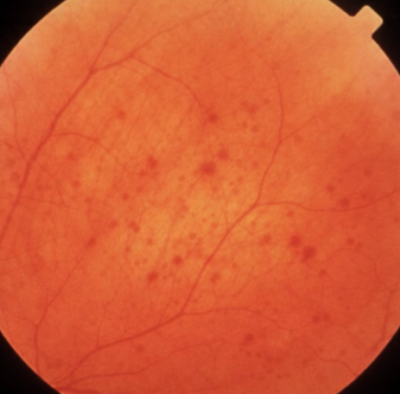

Its indicated in retinitis pigmentosa or (rp) is a group of genetic eye diseases where the light-sensitive cells, called “rods” and “cones” are dead. The main sign of the disease is the presence of dark deposits in the retina. The disease impacts central vision, which permits a person to read, drive, and perform activities that require sharp, straight-ahead vision.